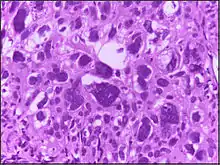

Large cell is a term used in oncology. It does not refer to a particular type of cell; rather it refers to cells that are larger than would be normally expected for that type. It is frequently used when describing lymphoma and lung cancer.

The phrase giant cell is also frequently used, especially with carcinoma.